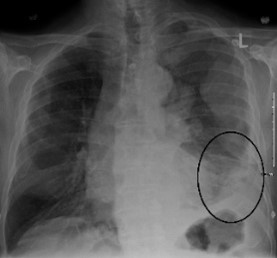

une poitrine avec un petit cercle sur le côté gauche« Cette étude représente une avancée importante dans le traitement du mésothéliome. Jusqu'à récemment, la chimiothérapie était la seule option de traitement pour cette maladie, mais maintenant nous pouvons en toute confiance proposer aussi l'immunothérapie. » - Dr Scott Laurie

Un essai clinique international publié dans The Lancet montre que l'immunothérapie améliore la survie des personnes atteintes d'un type agressif de cancer du poumon appelé mésothéliome pleural. L'essai de phase 3, coordonné par le Groupe canadien d'essais sur le cancer, a porté sur 440 patients atteints d'un mésothéliome avancé dans 51 hôpitaux au Canada, en Italie et en France.

Chaque année, plus de 30 000 personnes sont diagnostiquées avec un mésothéliome avancé. L'exposition à l'amiante est le principal facteur de risque.